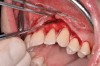

After initial incision techniques were done, a papillary-sparing incision was performed, leaving the crest of the papilla intact (Figure 10), thus allowing flap closure to be accomplished with a bed of autogenous tissue to support revascularization of the dermis/buccal flap complex. A full-thickness flap was then elevated to the mucogingival junction, after which a split-thickness dissection with a blunt elevator superior to the mucogingival junction area was performed to allow for release of tension and to let the buccal flap be mobilized coronally at closure (Figure 10). Care must be taken to avoid perforating the tissue in the region of the vestibuloplasty incision. After tension-free release of the flap, root planing of the exposed root surfaces was accomplished, followed by removal of the smear layer of cementum and chemical detoxification with a citric acid solution pH1 applied over the previously root-planed surfaces. After root preparation, the keratinized papillary tissues that remained following initial incisions were de-keratinized by using a #4 round diamond on a high-speed handpiece. De-keratinization provided a wound bed that enabled the dermal matrix graft to be secured and supported revascularization of the coronally repositioned buccal flap at closure.

Fig 10. Initial incisions, and blunt, split-thickness dissection for tension-free closure.

Figure 10